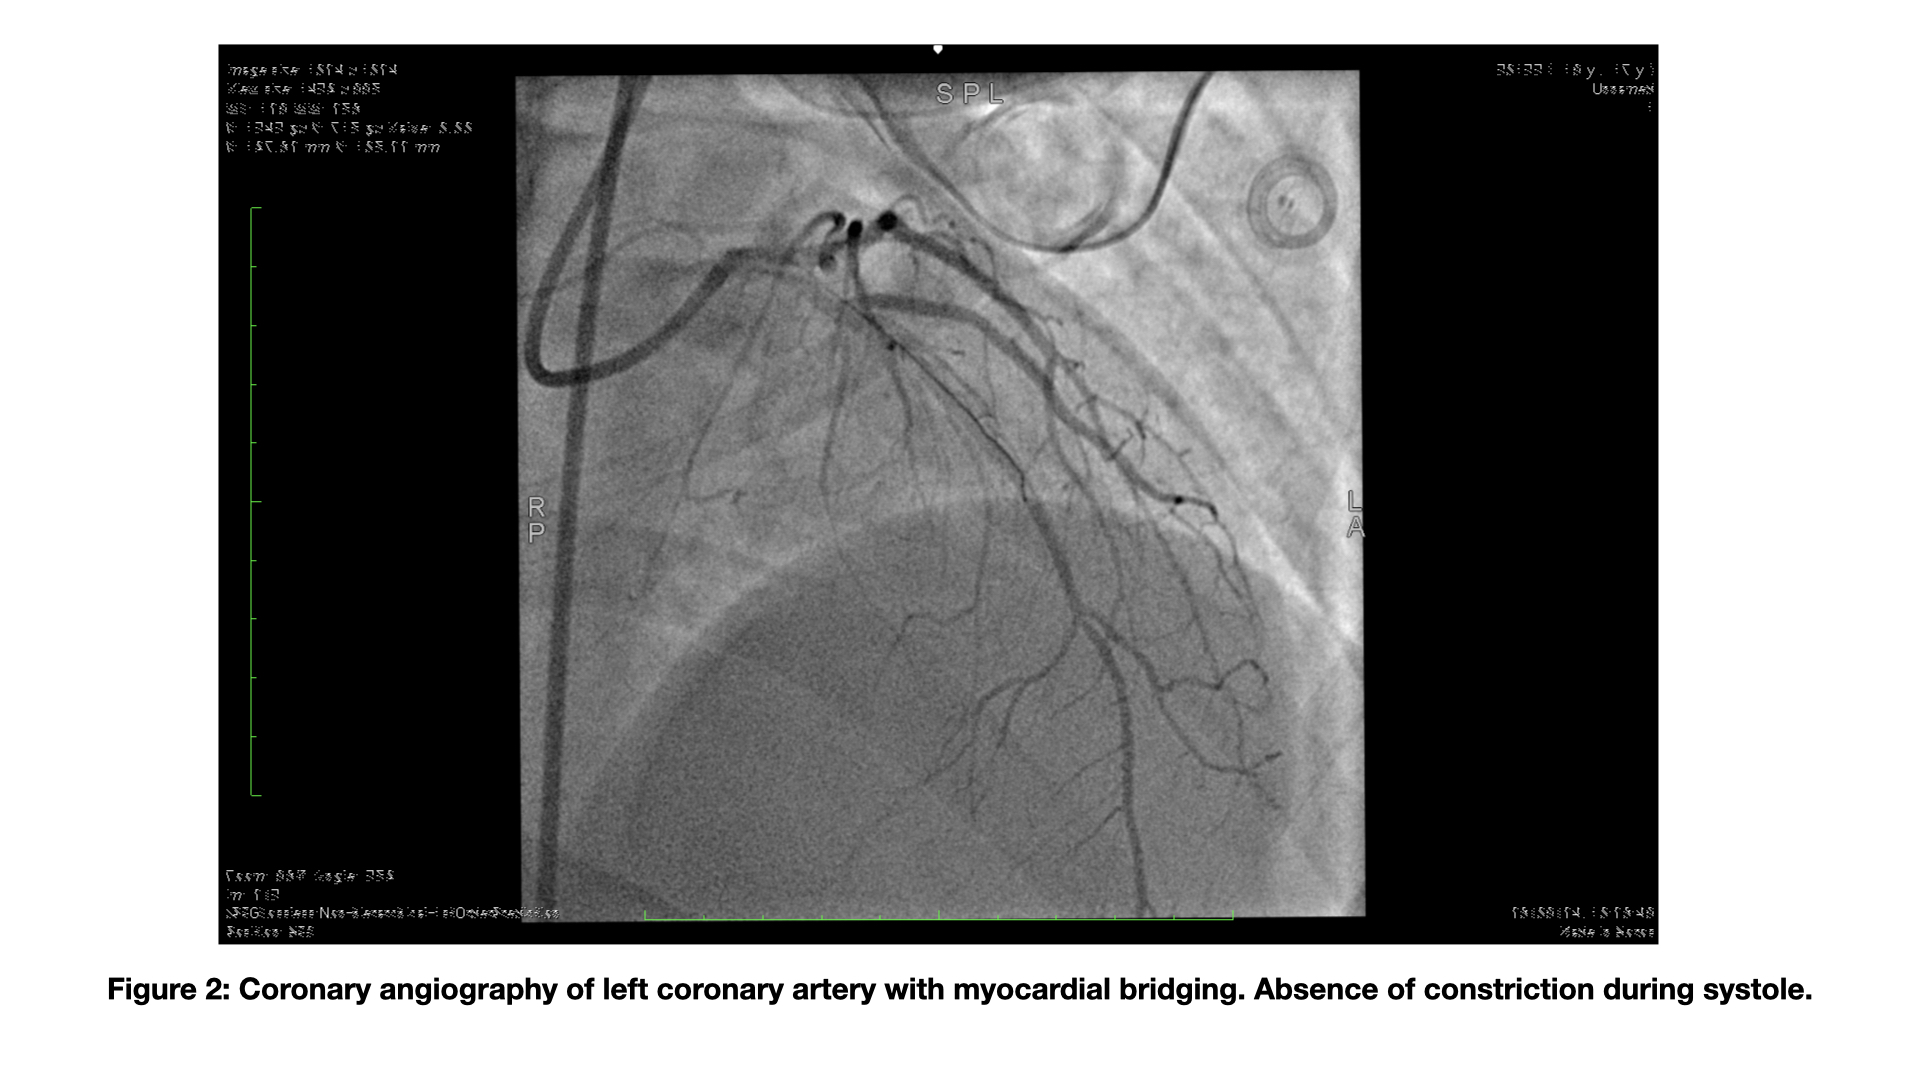

Background: Myocardial bridge (MB) is a tunneled segment of an epicardial coronary artery, running deep and for varying lengths in the context of the myocardial muscle. The clinical picture of MB ranges from the asymptomatic presentation to an acute coronary syndrome and sudden cardiac death. Case report : We present the case of a 18-year-old patient underwent pulmonary commissurotomy, cleft mitral valve closure and surgical correction of atrial septal defect when he was infant. During the recent follow-up, he experienced frequent ventricular extrasystoles organized into runs of non-sustained ventricular tachycardia during the exercise. Echocardiography demonstrated a normal biventricular function without severe residual valvular sequelae. No cardiomyopathy or late enhancement were detected by cardiac magnetic resonance evaluation. The patient was initially treated with beta-blocker and subsequently with amiodarone due to the persistence of arrhythmic burden during exercise. The diagnostic assessment was completed by coronary CT angiography, which revealed a long intramyocardial course of the left anterior descending artery, with length of 65 mm and maximum depth of about 3 mm. No significant luminal narrowing was observed during either systolic or diastolic phases; however, a filiform appearance of the vessel was noted in its distal segment. Following this radiological finding, the patient underwent functional evaluation with stress and rest myocardial scintigraphy, which demonstrated mild inducible ischemia involving the basal and parabasilar segments of the inferior and inferoseptal walls. According to the high anatomic risk features, we decide to assess the hemodynamic impact of MB with functional intracoronary evaluation. No systolic luminal narrowing was detected within the bridge segment like as no additional epicardial coronary abnormalities by coronary angiography (Fig.2).The invasive physiological assessment of MB was performed with RFR and FFR that were 0.93 and 0.9, respectively. The value of FFR remained unchanged after dobutamine intravenous infusion ( 20 μg/kg/min). Conclusion: This case highlights the use of FFR and RFR in assessing the functional impact of a MB. In this case,the patient was candidated to medical strategy increasing the beta-blocker and reducing the dose of amidoarone. Additionally, we have chosen precautionally to implant a loop recorder for monitoring the arrhythmic events; to date no repetitive events were detected.